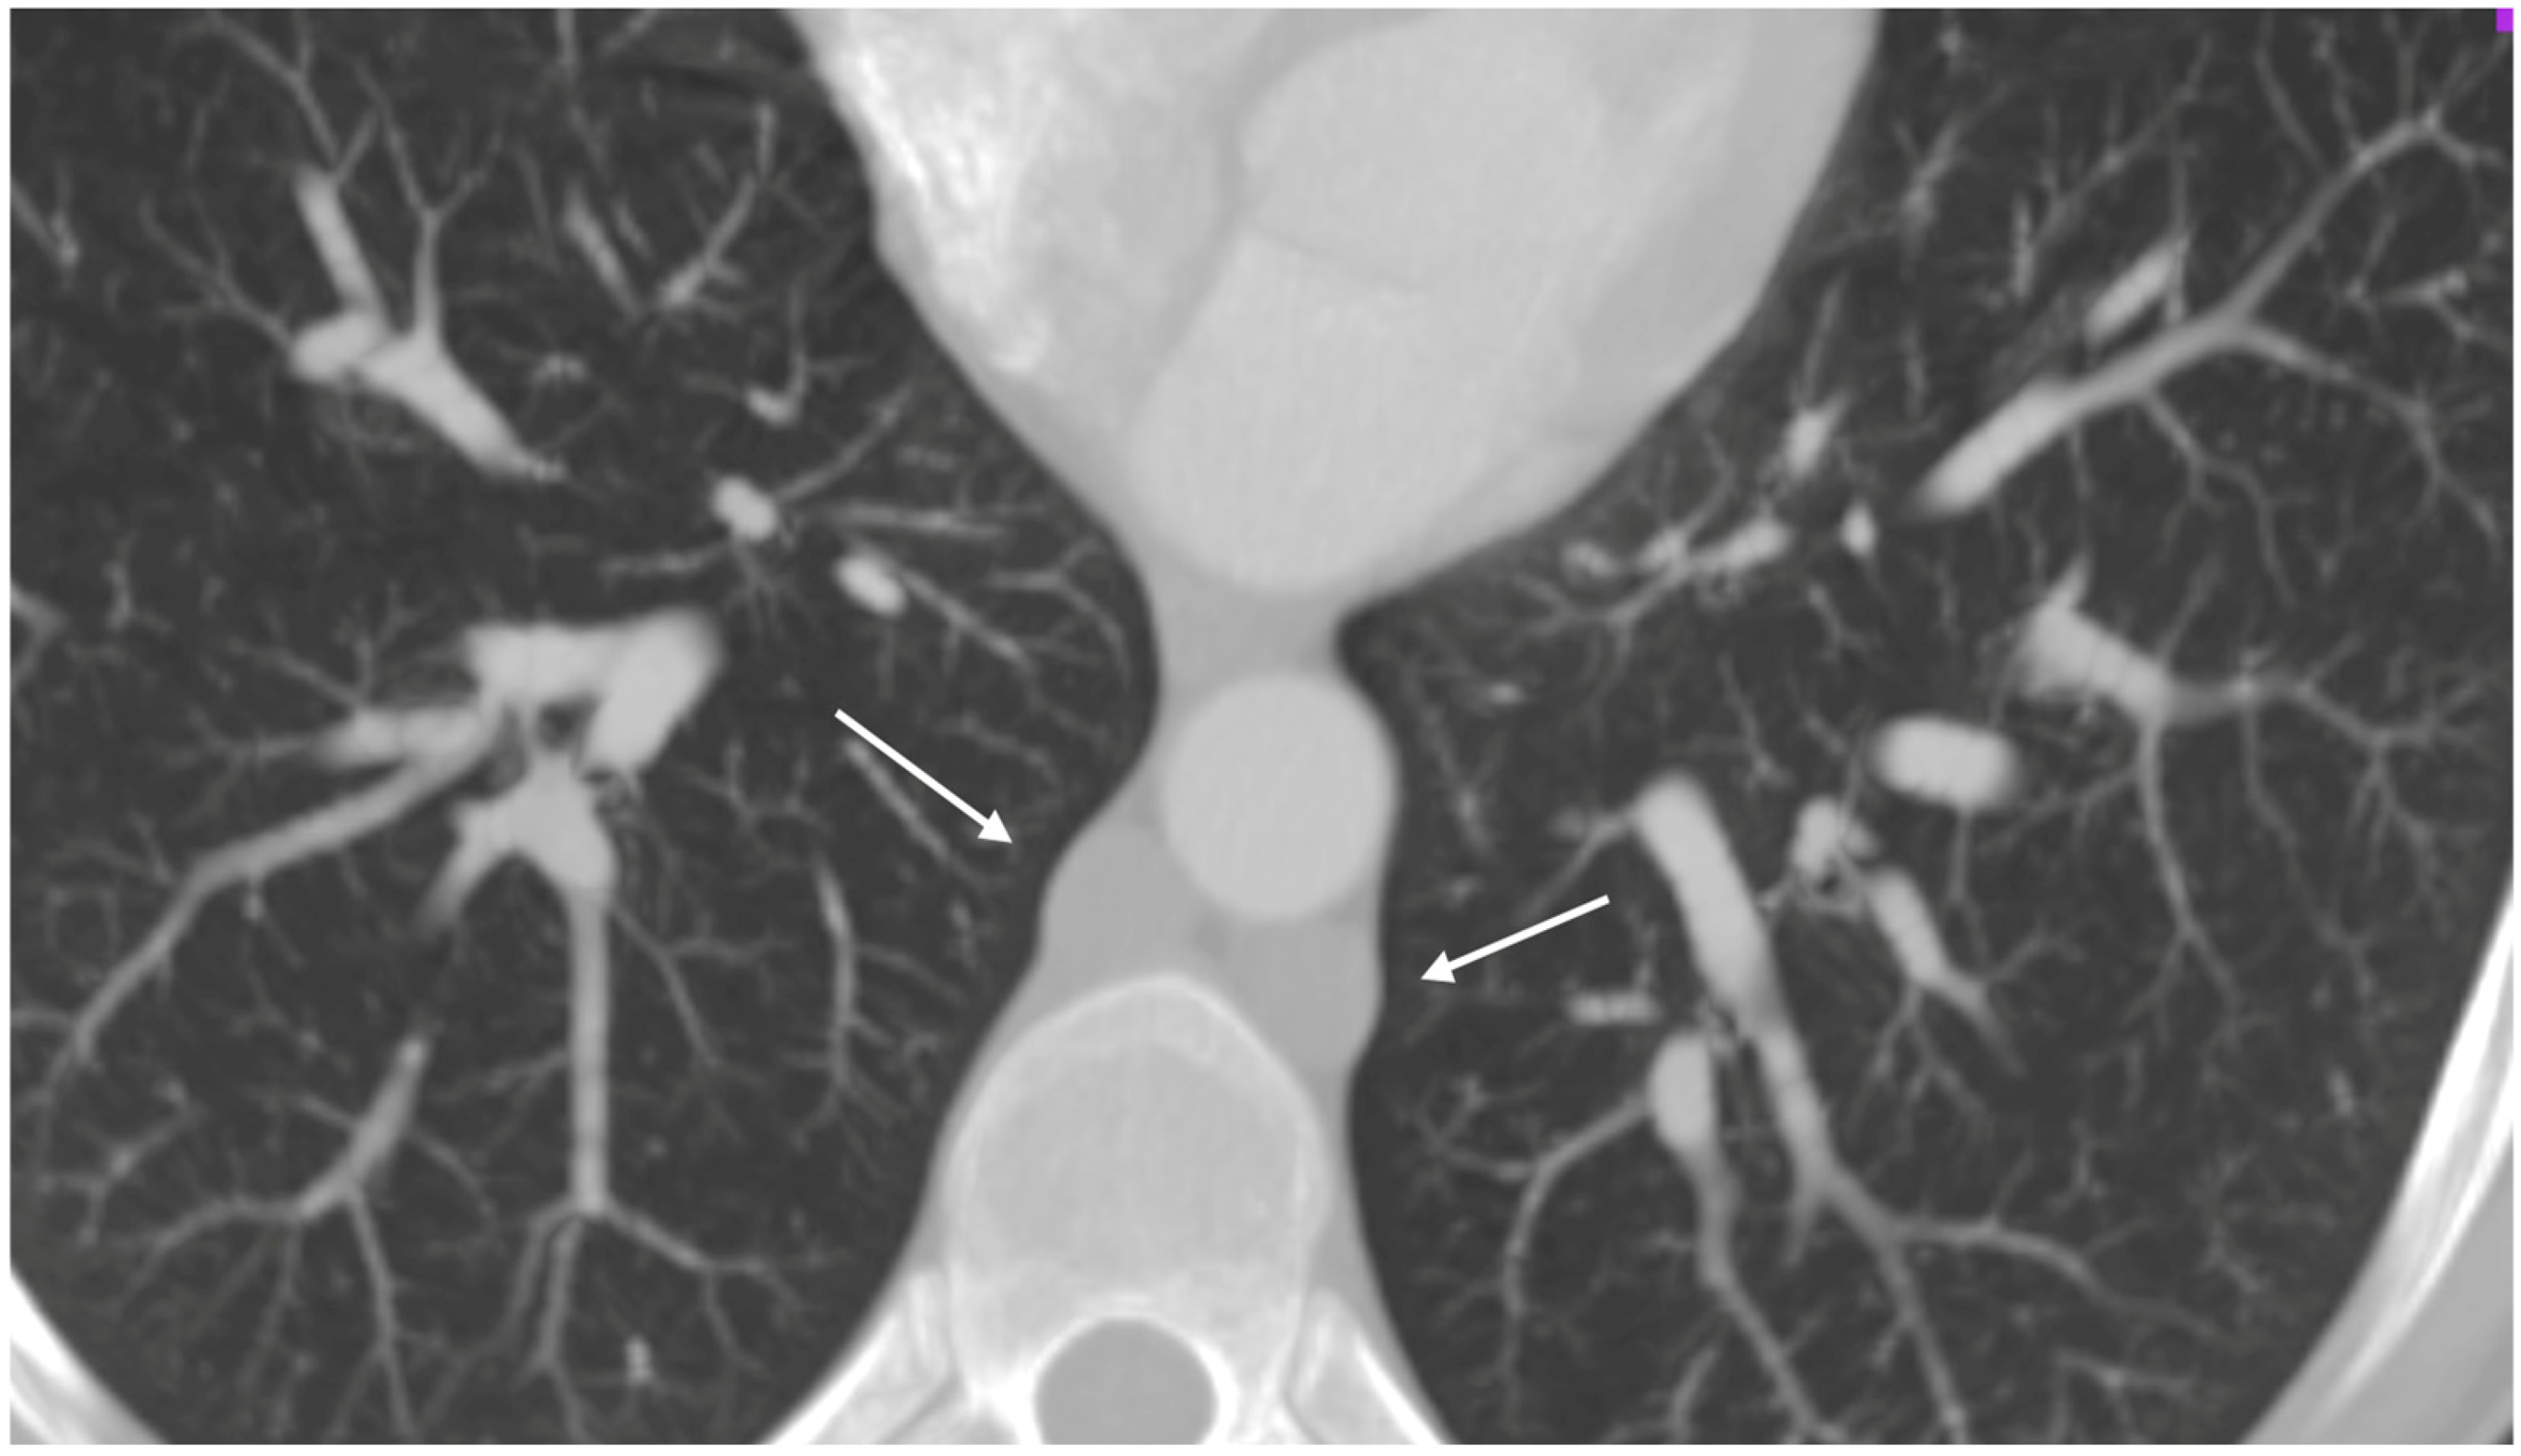

A respiratory alkalosis was found at the blood gas analysis so in suspicion of PE, Computed Tomography Angiography (CTA) was performed and did not detect any sign of pulmonary thromboembolism but azygos and hemiazygos vein dilatation (Figure 1) and a congenital abnormality of the IVC, in addition to DVT of iliaco-femoral veins with involvement of the IVC, renal veins, and mesenteric vein (Figure 2). Anticoagulation with low molecular weight heparin (LMWH) 1 mg/kg every 12 h subcutaneously was started.

Figure 1.

Thoracic angio-TC: dilated azygos and hemiazygos veins (arrows); no pulmonary embolism signs.